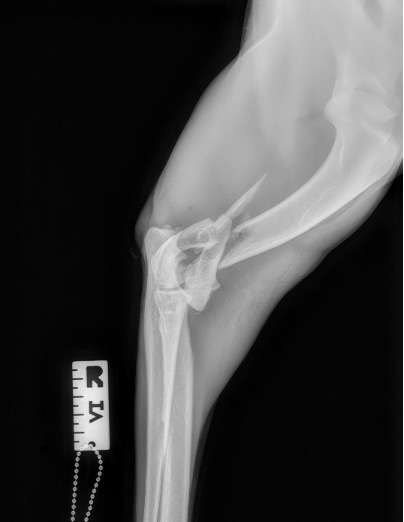

Figure 4 : Pré-Op

Notre préférence va vers le placement de deux plaques humérales : une médiale de la plus grande taille possible et l’autre latérale, généralement d’une taille inférieure à la première. Dans l’exemple 1 (chat européen), une plaque de 2 mm est utilisée médialement et une plaque de 1,5 mm latéralement. Dans l’exemple 2 (chien Malinois), une plaque de 3,5 mm est utilisée médialement et une plaque de 2,7 mm latéralement.